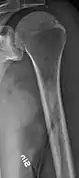

The diagnostic examination of a person with suspected multiple myeloma typically includes a skeletal survey. This is a series of X-rays of the skull, axial skeleton, and proximal long bones. Myeloma activity sometimes appears as "lytic lesions" (with local disappearance of normal bone due to resorption) or as "punched-out lesions" on the skull X-ray ("raindrop skull"). Lesions may also be sclerotic, which is seen as radiodense.[64] Overall, the radiodensity of myeloma is between −30 and 120 Hounsfield units (HU).[65] Magnetic resonance imaging is more sensitive than simple X-rays in the detection of lytic lesions, and may supersede a skeletal survey, especially when vertebral disease is suspected. Occasionally, a CT scan is performed to measure the size of soft-tissue plasmacytomas. Bone scans are typically not of any additional value in the workup of people with myeloma (no new bone formation; lytic lesions not well visualized on bone scan).

Femur with multiple myeloma lesions

Same femur before myeloma lesions for comparison